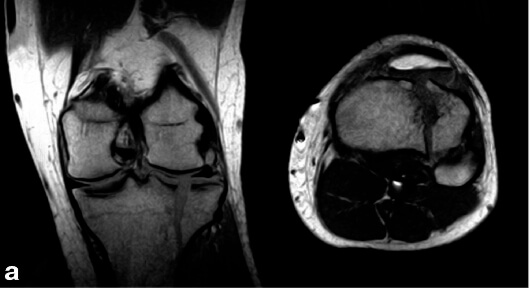

Эхо-картина здорового сустава

При проведении УЗИ специалист обращает внимание на параметры суставной полости и оболочки, хрящевой ткани и поверхностей костей, суставных сумок и заворотов, мягких тканей. Также УЗИ покажет наличие уплотнений, наростов, опухолей.

В протоколе УЗИ отображается норма и обнаруженные отклонения.

При обследовании здорового коленного сустава УЗИ показывает:

- ровные и четкие контуры костей с отсутствием деформаций;

- равномерный и имеющий однородную структуру гиалиновый хрящ;

- гипоэхогенность при сканировании заворотов и суставных сумок.

В норме при УЗИ отсутствуют:

- краевые остеофиты;

- выпот в суставной полости;

- отечность мягких тканей;

- визуализация синовиальной оболочки.

При обнаружении отклонений в строении и состоянии коленного сустава все показатели заносятся в протокол, к которому обязательно прикладываются снимки, сделанные в разных проекциях.